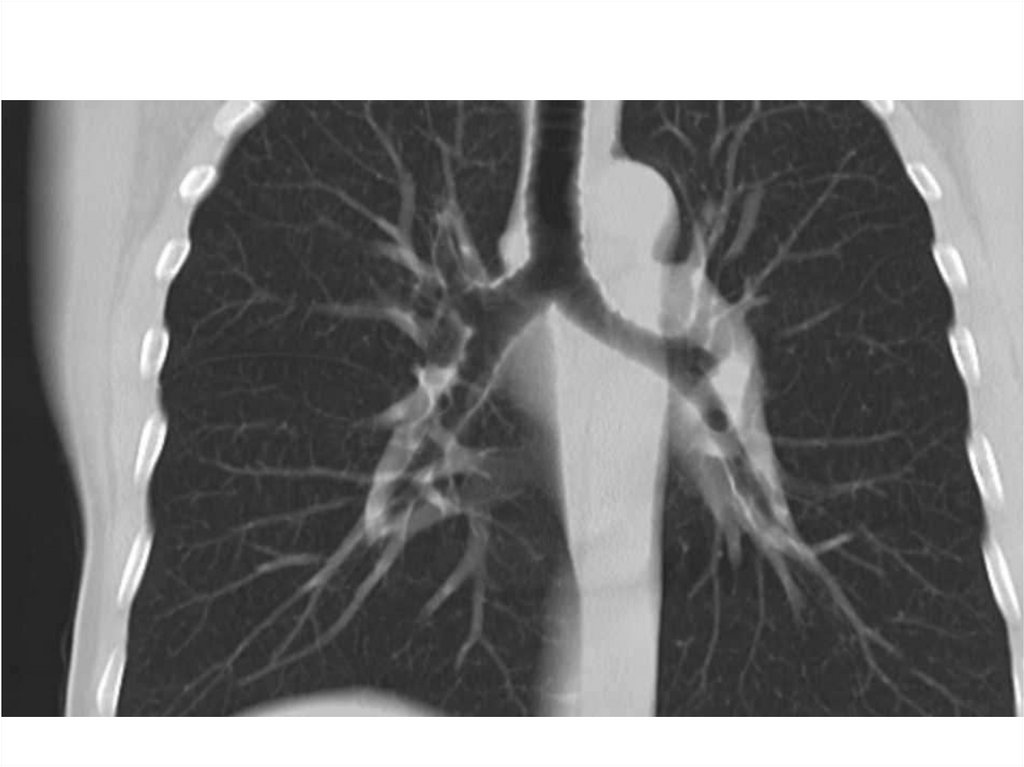

Компьютерная томография